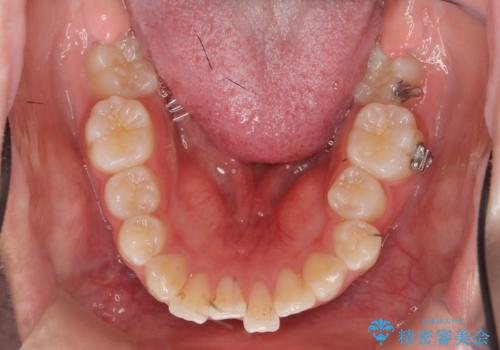

- 他院での矯正治療中に行かなくなってしまい、装置をつけたまま矯正治療の続きを希望され来院されました。

マウスピースでは並べることが難しい左下の奥歯を部分ワイヤー矯正で並べたのち、マウスピース矯正装置インビザラインで歯並びを整えていきます。